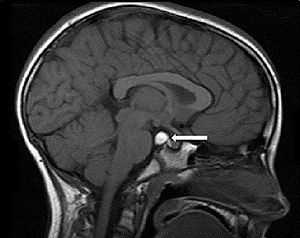

Интракраниальная герминома, известная также как дисгерминома или экстрагонадная семинома - дисонтогенетическая опухоль, наиболее часто встречающаяся у детей. Имеется тенденция к локализации по срединной линии - либо в пинеальной области, либо в области нижней стенки 3-го желудочка/ супраселлярной области.

- Пинеальная область (80-90%) - пинеальная герминома;

- Супраселлярная область (15-40%) - супраселлярная герминома;

Пинеальная область головного мозга — основное место расположения герминомы

возникает из-за поражения тканевой дифференцировки и переселения тканей на начальном этапе развития плода.

Чаще всего расположение новообразования — пинеальная область головного мозга, в связи с чем очень часто герминома провоцирует развитие гидроцефалии, когда лишняя жидкость скапливается в мозге, на этом фоне возникают перечисленные симптомы:

![Герминома головного мозга]()

Герминома головного мозга составляет лишь 2% от всех внутримозговых опухолей, однако она является самой часто встречающейся опухолью глубинных структур головного мозга (пинеальной области, шишковидного тела, III желудочка и гипофизарной области). На долю гермином головного мозга, расположенных в пинеальной области, приходится около 56%. Герминомы головного мозга, локализующиеся в области гипофиза, составляют 25%. В 75% случаев герминома головного мозга представляет собой единичную опухоль, в 25% случаев она носит множественный характер.